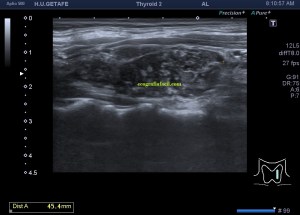

El paciente viene por un bulto en la parte derecha de la espalda, en la región paradorsal alta. Con una sonda de alta frecuencia accedo a la región, que era palpable. Lo primero que observo es que la transmisión del paciente no es buena, esto que a veces pasa que encuentras pacientes, que no sé explicar el motivo, no transmiten bien.

Me da para observar que en la zona de palpación encuentro, profundo en la imagen, un formación hiperecogénica, que está dentro de un músculo. Antes de detallar los hallazgos de la imagen lo que quise fue reconocer bien la anatomía. La piel y el tejido celular subcutánea era muy fácil, también saber que esta anatomía superficial estaba intacta y que la lesión estaba intramuscular, pero me encontraba dos planos musculares, uno superficial, el otro profundo, el profundo con la lesión.

Me tuve que ir al atlas de anatomía para saber cuál era el músculo que estaba debajo del músculo trapecio, que tenía claro que era el superficial. Bien, el músculo que ocupaba el segundo plano en profundidad era el músculo Romboides, que te enlazo para que sepas más de su posición y función.

El protocolo es el típico, cortes en eje corto y largo, con doppler, para comprobar vascularización, como línea roja del lipoma. Imágenes 3,4 y 6.

Después con la radióloga, hicimos una imágenes con «panoramic view» que te dan un detalle de las anatomía con respecto del lado contralateral, sano. Imagen 1.

La lesión era ovalada, hiperecogénica, ocupaba gran parte del músculo, pero respetaba parte de este, que era hipoecogénico (imagen 5), recuerda que así es por definición y que ésta ecogenicidad del músculo es referencia para el resto de ecogenicidades del aparato locomotor. Como te he contado, no había doppler color ni en modo angio.